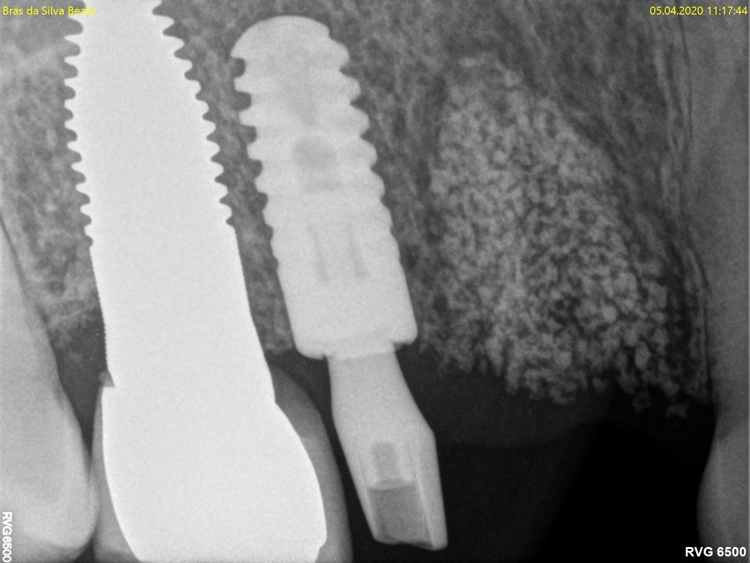

Nach der ersten klinischen Befundaufnahme und Fotodokumentation der Ausgangssituation (Abb. 1) wurde zur Ergänzung des klinischen Befundes eine Einzelzahnaufnahme erstellt (Abb. 2). Vom Oberkiefer wurde eine Abformung genommen, um eine Tiefziehschiene herzustellen. Diese wird direkt am OP-Tag genutzt, um eine provisorische Krone herzustellen.

Aufgrund der traumatischen Extraktion des ankylosierten Zahnes, die zu einer Osteotomie wurde (Abb. 3), fehlten die vestibuläre und palatinale Lamelle (Röntgenkontrollbild während der Osteotomie, Wurzelrest noch vorhanden Abb. 4). Dieser Wurzelrest wurde entfernt. Bei dem geringen Restknochenvolumen war eine Sofortimplantation nicht mehr indiziert.